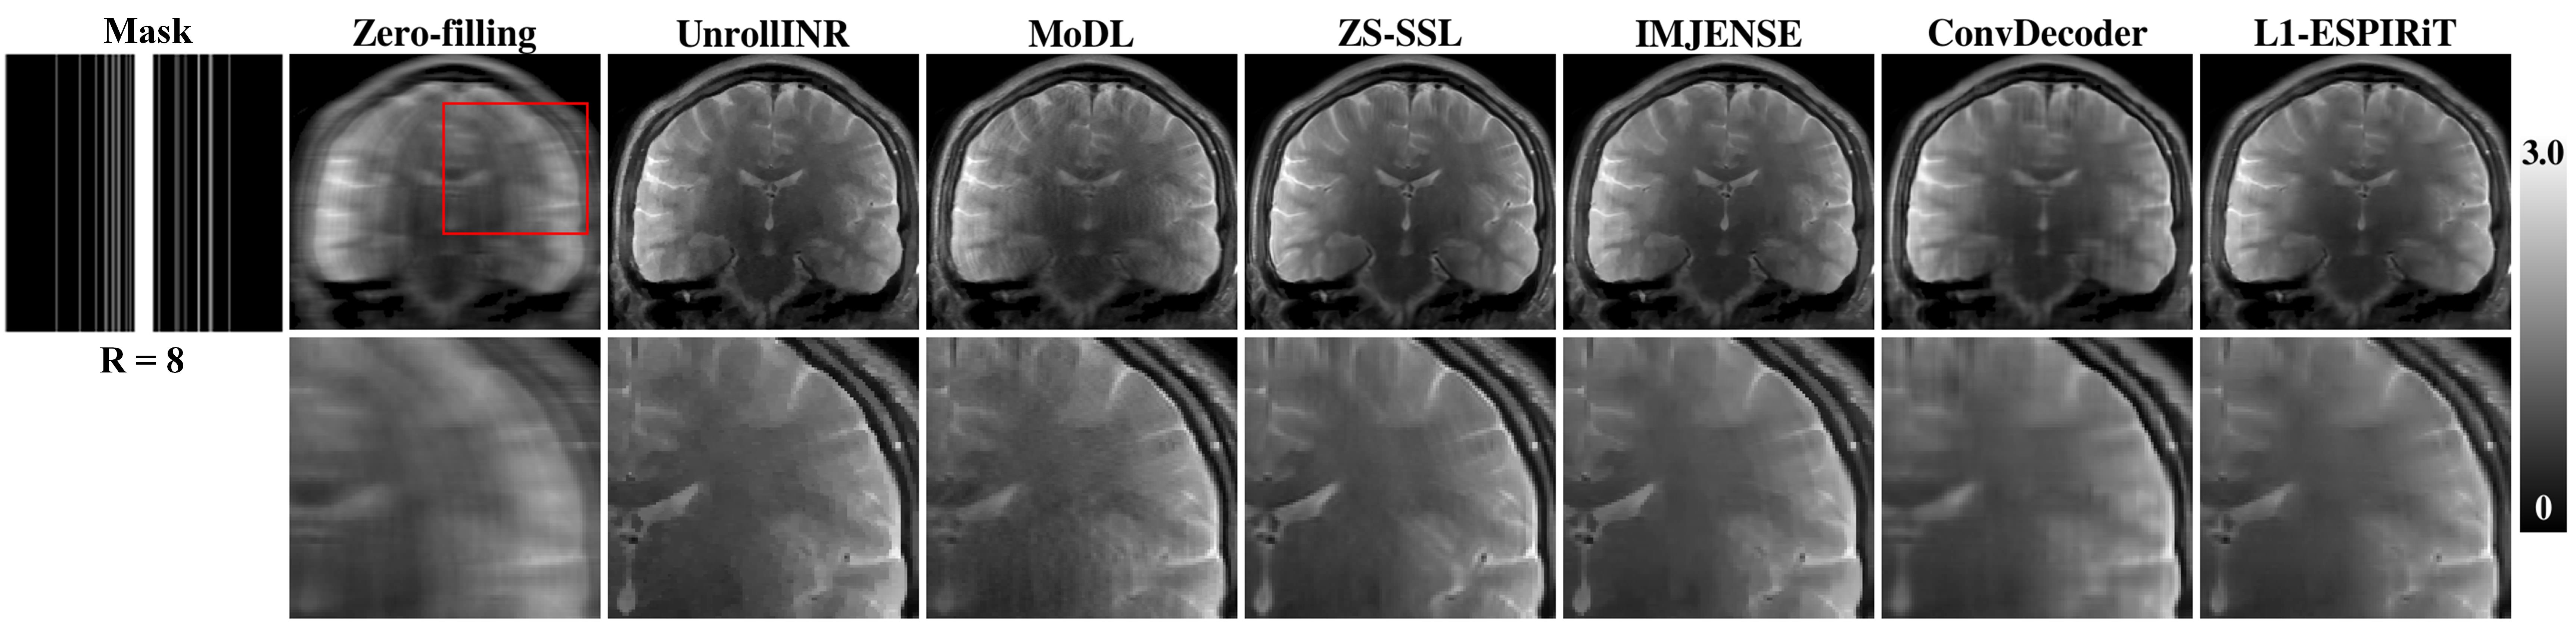

Fig. 3 presents the retrospective reconstruction results of all comparative methods on a randomly selected brain slice under different acceleration rates. According to the quantitative evaluation metrics of the reconstructed images, the proposed UnrollINR again achieves the best reconstruction performance. Visually, UnrollINR also demonstrates effective artifact removal and fine detail recovery. The supervised method MoDL shows noticeable residual artifacts at high acceleration rates. The unrolled method ZS-SSL loses fine details in its reconstructed images. Other comparative unsupervised methods exhibit significant noise and residual artifacts.

Fig. 4 presents the prospective reconstruction results of all comparative methods with an acceleration rate of R = 8 and an actural undersampling rate of 12.5%. To facilitate comparison, locally magnified views of each reconstructed image are provided. The undersampling mask, which has an ACS size of 26, is displayed on the far left of the figure. As shown in the results, the reconstructed images of L1-ESPIRiT and ConvDecoder appear overly smooth; aliasing artifacts persist in the reconstructions of ZS-SSL and IMJENSE; while the MoDL method exhibits image blurring and noise. In contrast, UnrollINR demonstrates superior performance in artifact suppression and detail preservation, highlighting its precise reconstruction capability.